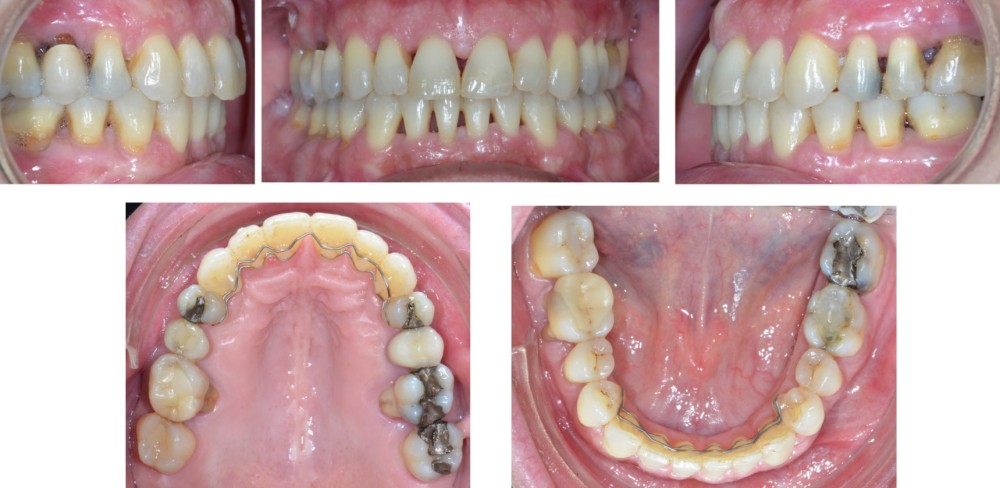

À l’examen endo-buccal (fig. 2), on note une formule dentaire complète (absence des 8) avec présence de restaurations multiples étanches, un bon contrôle de plaque et une parodontite de stade 4 grade C stabilisée [3], des récessions gingivales et des mobilités dentaires généralisées (degré 2, classification de Miller). L’arcade mandibulaire présente une courbe de spee importante avec égression du bloc incisivo-canin. Les milieux inter-incisifs sont alignés, le recouvrement est normal, le surplomb est augmenté à 3 mm et associé à des diastèmes et de la vestibulo-version des incisives maxillaires. Les relations antéro-postérieures canine et molaire sont en Classe I d’Angle.